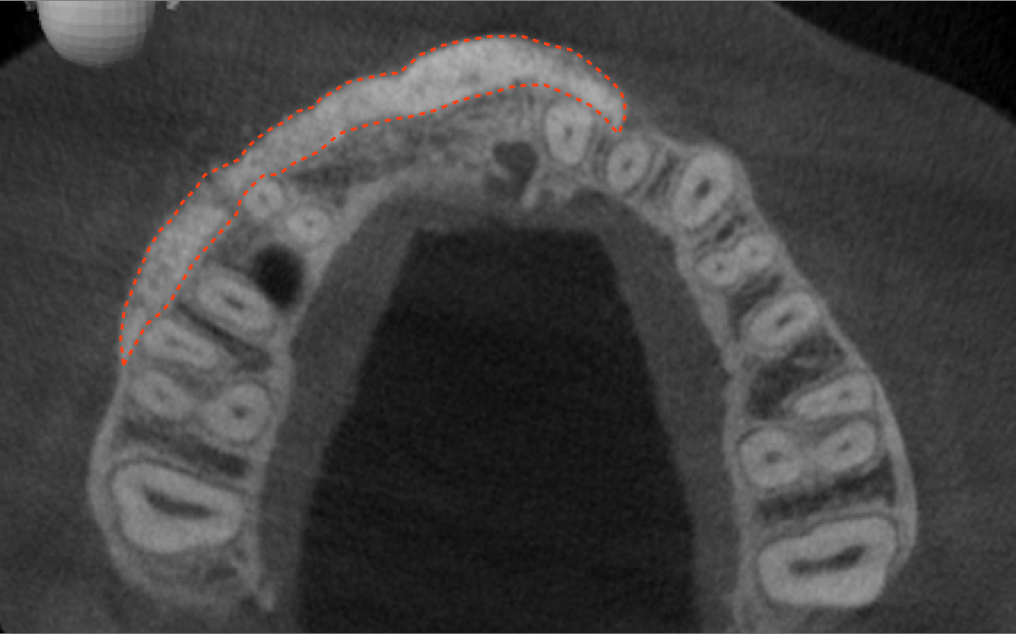

Tomographic images revealed a large tridimensional defect, with vertical and horizontal loss of bone extending to the apical third of teeth Nos. 6 and 8. Additionally, a buccal bone dehiscence was evident on tooth No. 5, and thin labial plates secondary to the orthodontic movement were present in several areas (Figure 3 and Figure 4).

Fig 3. Tomographic images revealed a tridimensional defect extending to the apical third of teeth Nos. 6 and 8, a buccal bone dehiscence on tooth No. 5, and associated thin labial plates.

Figure 3

Fig 4. Tomographic images revealed a tridimensional defect extending to the apical third of teeth Nos. 6 and 8, a buccal bone dehiscence on tooth No. 5, and associated thin labial plates.

Figure 4